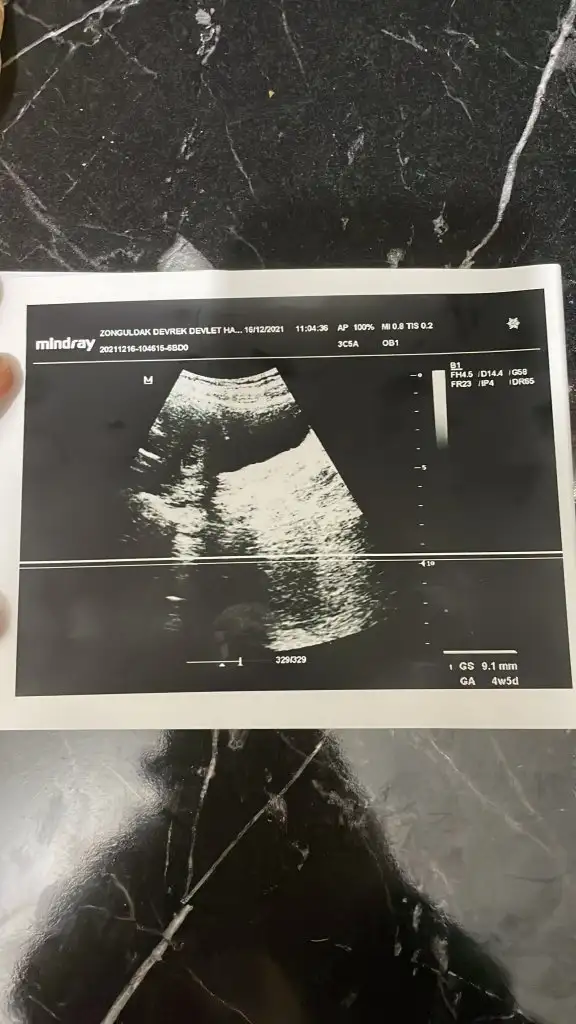

O Mm kesenin boyutudur. Henüz bebek bile oluşmamış olur bu haftada. 2 hafta sonra giderseniz daha net bilgiler elde edersinizmerhaba kızlar bende bir soru sormak istiyorum doktora gittim ultrasyon ile muayene etti iki ayrı ustrasyon kagıdı verdi birinde 4+5 9.1 mm birinde 4+6 9.8mm yazıyordu bu ne anlama geliyor kan degerinde 5355 cıkmıstı doktor bi acıklama yapmadı ikiz olma durumu varmıdır size nasıl kahıt vermişlerdi hatırlıyormusunuz